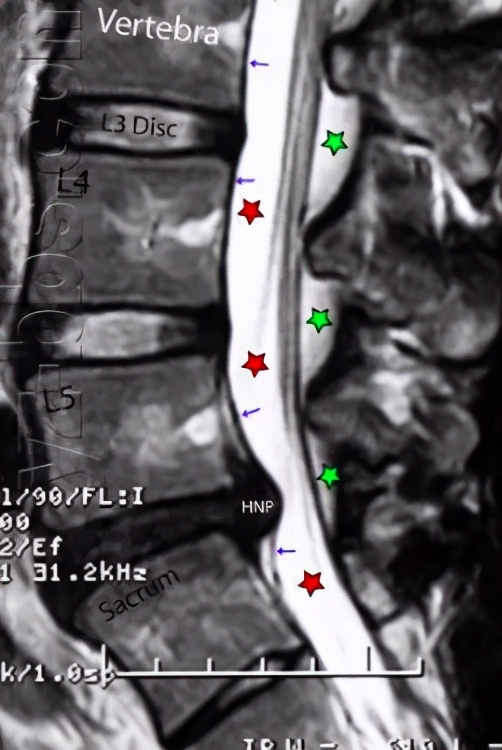

通俗一点说:X线可以看脊柱的生理曲度是否正常、有没有椎体的滑脱、有没有合并脊柱侧弯或后凸;CT在显示骨性病变,如椎间盘钙化时候更有优势;而核磁共振可以清楚看到腰椎间盘有没有突出,脊髓和神经根有无压迫都可以了如指掌。